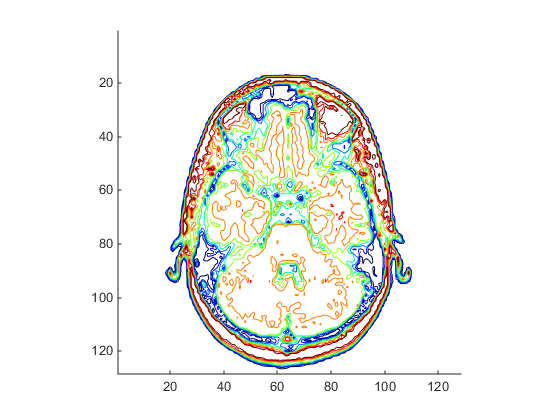

Визуализируйте данные МРТ как объемные данные, поскольку они представляют собой набор фрагментов, последовательно проходящих через объект 3-D. Использовать contourslice для отображения контурного графика объемного фрагмента. Создайте контурный график с той же ориентацией и размером, что и изображение, созданное в первой части этого примера.

Для улучшения видимости деталей в этом контурном графике используется jet colormap. brighten функция уменьшает яркость значений цвета.

cm = brighten(jet(length(map)),-.5); figure colormap(cm) contourslice(D,[],[],image_num) axis ij xlim(x) ylim(y) daspect([1,1,1])

В отличие от изображений, которые являются 2-D объектами, контурные фрагменты являются 3-D объектами, которые можно отображать в любой ориентации. Например, можно отобразить четыре фрагмента контура на виде 3-D.